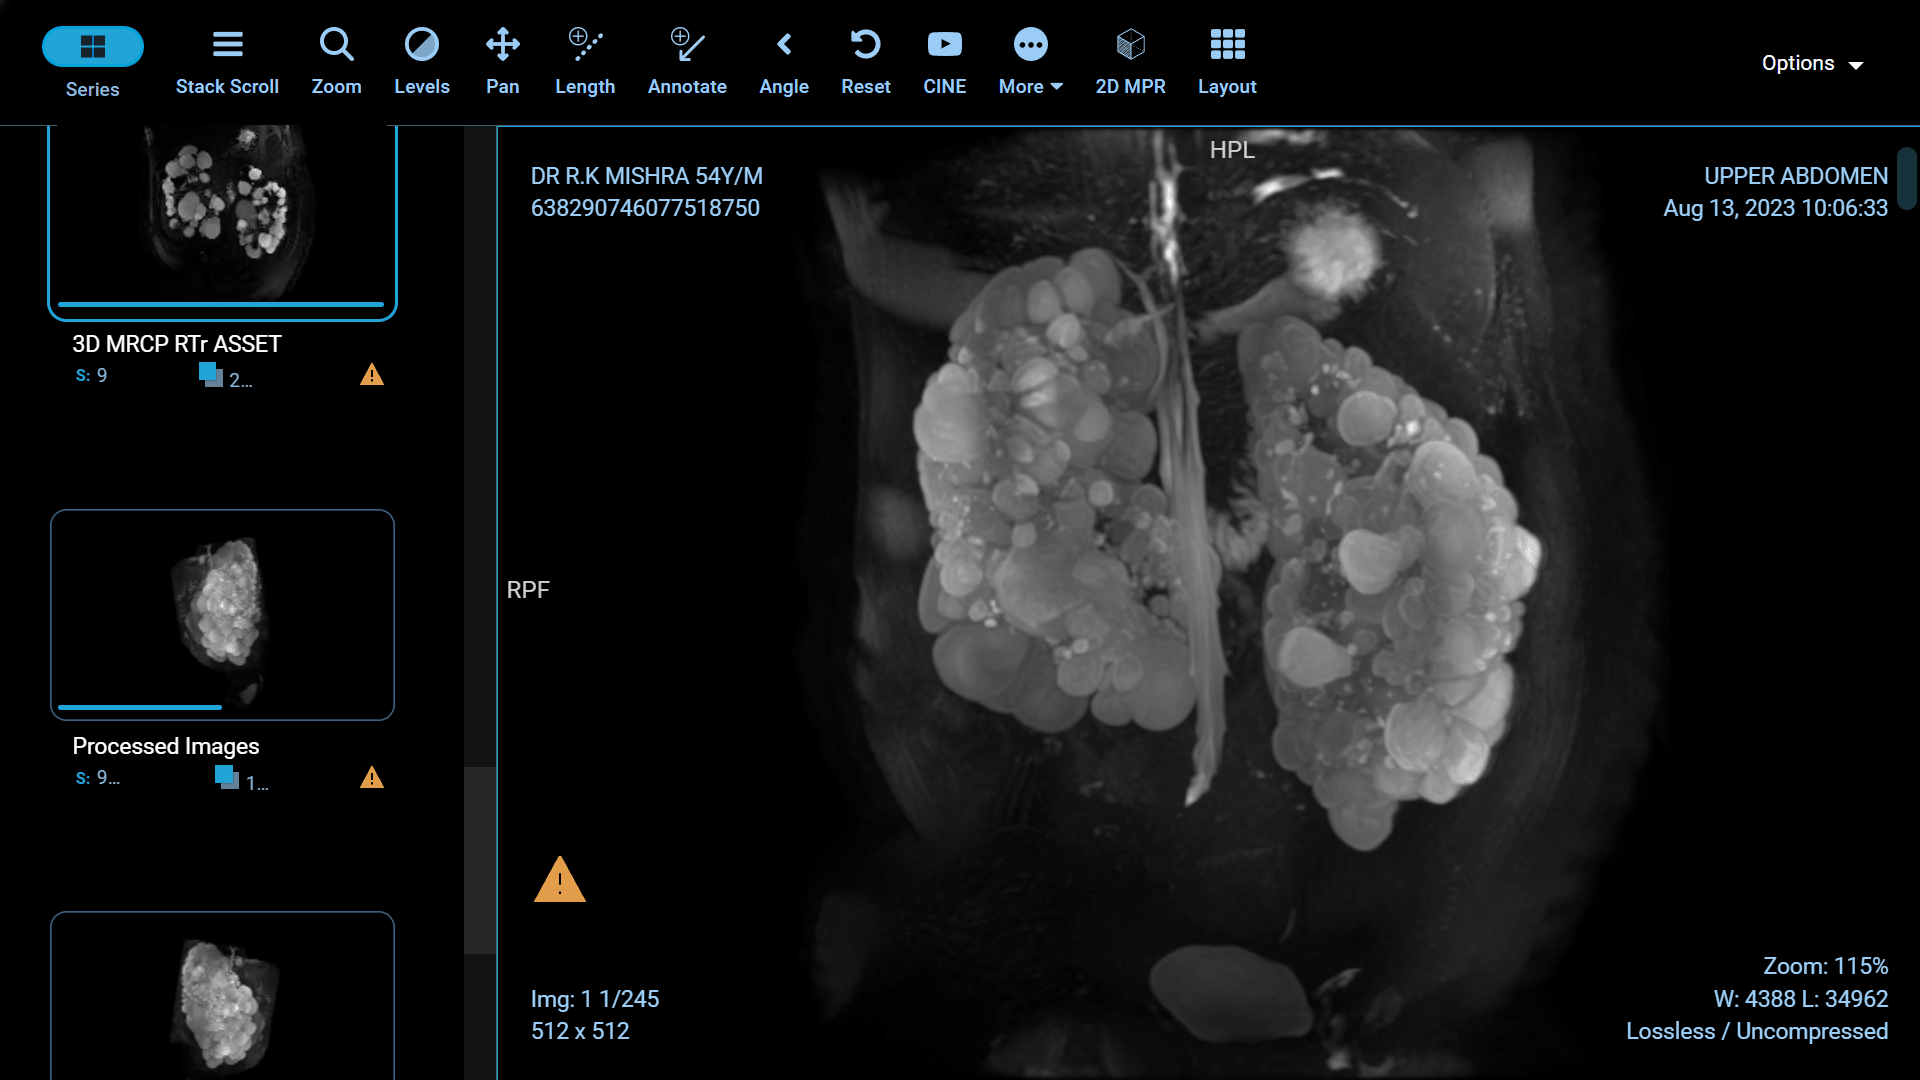

Polycystic Kidney Disease (PKD) is a genetic disorder characterized by the formation of fluid-filled cysts in the kidneys, which can lead to renal failure if left untreated. Fortunately, recent advancements in medical science have paved the way for more effective treatments and improved the quality of life for those affected by this condition. In this article, we will explore some of the groundbreaking innovations in PKD treatment.

Foam sclerotherapy is a medical procedure that involves injecting a specialized foam directly into kidney cysts. The foam is made by mixing a liquid sclerosing agent, typically a solution of alcohol or polidocanol, with air or gas to create a stable, persistent foam. This foam is then injected into the cyst through a thin needle under ultrasound or CT guidance.

The success of foam sclerotherapy lies in its ability to cause intentional injury to the cyst lining, promoting inflammation and scarring. This process leads to the collapse and sealing of the cyst, preventing further fluid accumulation and reducing the cyst's size.

Preservation of Healthy Kidney Tissue: Unlike some other treatments, foam sclerotherapy specifically targets the cyst, leaving the surrounding healthy kidney tissue intact. This is particularly important for individuals with only one functioning kidney.

Potential for Multiple Cysts: Foam sclerotherapy can be used to treat multiple cysts in one or both kidneys during a single procedure, reducing the need for multiple interventions.